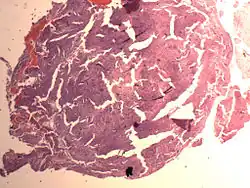

Endometrial Stromal Nodule

An endometrial stromal nodule is a noninfiltrative, circumscribed proliferation of endometrial stromal cells and is a benign subtype of endometrial stromal tumor. The appearance of the cells is identical to normal endometrial stromal cells. This can only be differentiated from low-grade endometrial stromal sarcoma by confirming lack of infiltration.

The differential includes cellular leiomyoma. Diagnosis may be aided by immunostaining; endometrial stromal nodules are positive for CD10; leiomyomas are positive for caldesmon and desmin (and sometimes CD10).